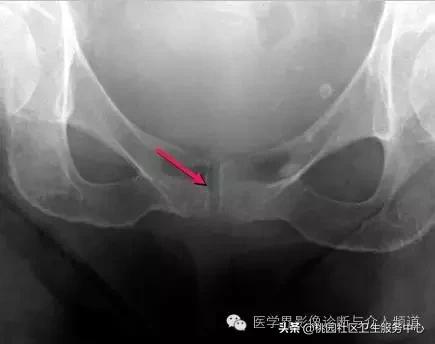

常见于膝盖、耻骨联合、臀部、尺骨三角纤维软骨复合体、肩关节。

耻骨联合软骨钙化